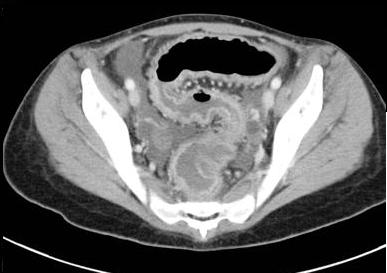

. Image TDM du maladie de

Crohn dans phase aigue est image

de epaissisement parietale avec oedeme sous muqueuse

discontinunite et signe de peigne " comb sign ". En phase

chronique cicatricielle ,aspect radiologique est image

epaissisement homogene de la paroi avec infiltration graisseuse parietale ou mesenterique

en forme de image de cible " fat halo sign". Stenose ,fistule et

abces sont des images de sa complication .

Image de

hypervascularisation " Comb sign " et epaissisement

de la paroi du ileon se voyait si nette sur les

coupe TDM axiale |